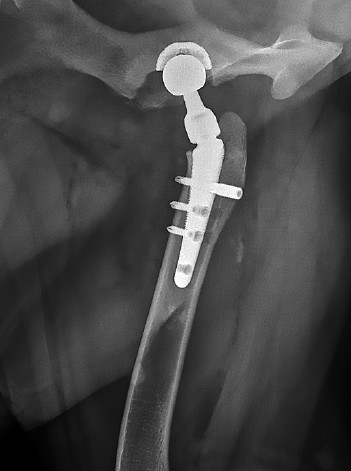

Исследования явились результатом длительного поиска надежной стабилизации импланта и поэтапной его остеоинтеграции, ведь совершенствование технологии эндопротезирования это повышение стабильности фиксации, снижение риска инфекций и улучшение биосовместимости имплантов. В этой связи, согласно клиническому опыту авторов, при соблюдении порядка введения винтов по технологии компании Kyon, частота осложнений в виде асептической нестабильности ножки эндопротеза составляет 8 % (рис. 2). К рентгенологическим признакам нестабильности относятся: перелом или миграция импланта, выраженный остеолиз вокруг ножки, а также периостальная и эндостальная костная реакция. Ранее для фиксации бедренного компонента (ножки) V@art размеров M и L применяли 5 винтов, включая один бикортикальный. Однако, на практике установка дистального винта в отверстие № 5 вызывала технические трудности. После отказа от его использования, частота асептической нестабильности не возросла. Дополнительное введение второго проксимального бикортикального винта привело к значительному снижению риска нестабильности (менее 1 %), а также улучшило равномерное прилегание ножки к медиальному кортикальному слою (рис. 1).

Рис. 1. Послеоперационная рентгенография проекция «Йога»

Источник: составлено А.М. Пантюлиным, И.Ф. Вилковыским.

Fig. 1. Postoperative radiography, “Yoga” projection

Source: compiled by A.M. Pantyulin, I.F. Vilkoviskiy.